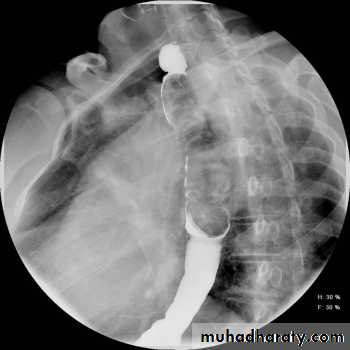

CausesEsophageal atresia

Types:• isolated atresia 8%

• Proximal fistula with distal atresia 1%

• Proximal atresia with distal fistula 85%

• Double fistula with intervening atresia 1%

• Isolated fistula [H-type] 4%